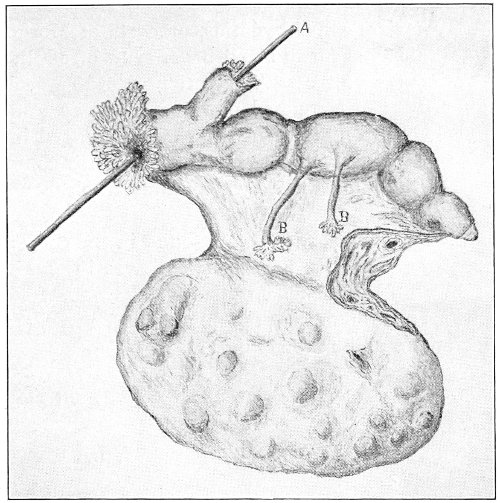

Cysts of the gland may be unilocular if formed at the expense of a single lobule of the gland, or multilocular if several lobules enter into their formation. These cysts may attain the size of the fetal head (Fig. 18).

Cysts of the gland or of the duct are formed by retention of the cyst-contents. The retention is due to occlusion of the duct, usually the result of inflammation. In some cases the duct remains pervious, and the retention is due to the altered character of the secretion of the gland, which becomes too viscous to pass, except under unusual pressure, along the duct.

These cysts contain clear yellow or chocolate-colored 42 fluid. The diagnosis of cyst of the vulvo-vaginal gland is usually not difficult. If we are in doubt in regard to the fluid character of the tumor, this may be determined with the exploring-needle.

Inguinal hernia, hydrocele of the canal of Nuck, cysts of the round ligament, and sacculated cysts of old hernial sacs may be mistaken for cysts of the vulvo-vaginal glands. In such cases, however, the tumor lies more in the upper and outer part of the labium majus, and extends to, and may be connected with, the external inguinal ring.

Cysts of the vulvo-vaginal glands should be treated by free incision and packing, or by extirpation. If the sac is emptied by the aspirator or by a small incision, it will refill. The best method is to extirpate the cyst. In case there has been no inflammatory action binding the cyst to surrounding structures, extirpation without rupture is easy. If rupture occurs, the cyst-wall may be dissected off with the knife or removed with the curved scissors. The wound may be immediately closed with deep and superficial sutures.